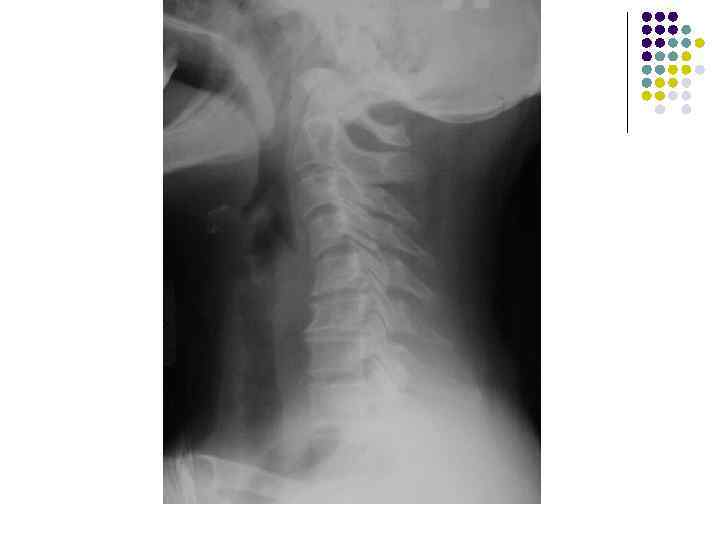

l l l На рентгенограмме шейного отдела позвоночного столба в боковой проекции определяется: выраженные дистрофические изменения за счет остеохондроза - значительное, неравномерное сужение межпозвонковых пространств с нарушением их правильной клиновидной формы, выраженный субхондральный остеосклероз, значительные костные разрастания по передним краям тел позвонков. Наиболее ярко эти изменения представлены в сегментах С-5, 6, 7. Помимо этого, в этих же сегментах фиксируются дистрофические изменения дугоотростчатых суставов – сужение рентгеновских суставных щелей, субхондральный остеосклероз и костные разрастания по краям суставных поверхностей. Выпрямление физиологического лордоза. Признаки системного нарушения статики тел позвонков в виде симптомов кифотической установки. Деструктивных изменений нет Заключение: Комплекс дистрофических изменений шейного отдела позвоночного столба в виде остеохондроза и артроза дугоотростчатых суставов с преимущественными проявлениями в нижних сегментах отдела. Нарушение статики тел позвонков

l На рентгенограмме шейного отдела позвоночного столба в боковой проекции определяется: выраженные дистрофические изменения за счет остеохондроза с преимущественными проявлениями в сегменте С 5 -6 – сужение и деформация межпозвонковых пространств, выраженный субхондральный остеосклероз, значительные костные разрастания по краям тел позвонков. Выпрямление физиологического лордоза. Признаки нарушения положения тела С 4 (симптом «распорки» )